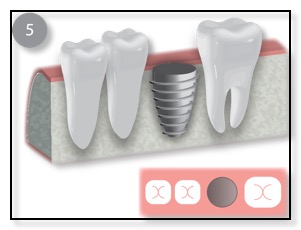

There are two basic types of bone grafting for dental implants. The most common one is after you have a tooth extracted, or if you lost a tooth awhile back. There could be insufficient bone support in such scenarios and thus a bone graft is needed. (See diagram above.) Dr. Tsai will numb the gum before making an incision to expose the area requiring the graft, or if the tooth was just extracted, then she will gently push the gum back to expose the existing bone. She will then place the graft, anchoring it in place if necessary, before covering it with a membrane and suturing the gum back in place. You will be given instructions on how to care for the bone graft site, and how to keep it clean. Bone grafts generally need to be left to heal for several months, although, if the amount of bone grafted was relatively small, it may be possible to place the implant at the same time.

Once the bone is heal, Dr. Tsai will place the implant, allow that to integrate with the bone, and then restore with an Abutment and Crown.